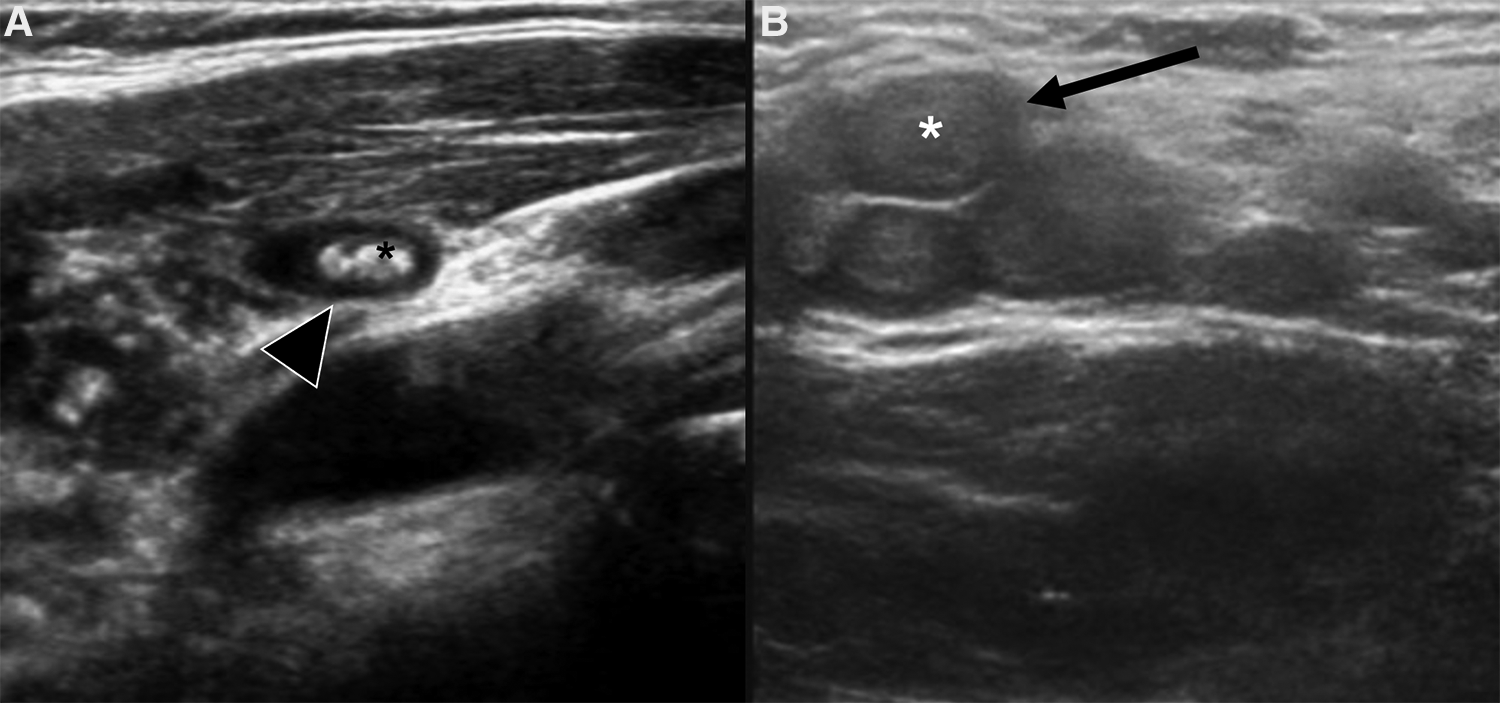

Despite the different pathogenesis, clinical presentation and genetics, CH and IH have almost the same imaging characteristics, particularly during the proliferative phase. However, CHs are more likely to have aneurysms, larger venous components, intravascular thrombi and even high flow velocity at birth, compared to their infantile counterpart (19), ancillary findings that must be carefully be searched for. US demonstrates a well-demarcated tumor with variable echogenicity and high vascularity, showing more than 5 vessels/cm with high flow velocities at Color Flow Doppler during the proliferating phase (20) (Figure 2). During the involuting and involuted phases, flow velocity and vessel density will decrease. Due to its considerable abilities in the assessment of intra-lesional blood flow, CEUS is making its way as a powerful additional tool in the assessment of orbital space-occupying lesions (21, 22). At CEUS hemangiomas are hyper-enhancing during both the early and late arterial phase. Enhancement of IHs starts as a peripheral nodules and then progressively expands in a centripetal pattern and completely fills the lesion (Figure 3). During the delayed phase, hemangiomas keep showing sustained enhancement relative to surrounding tissues.

Figure 3. Us and CEUS of a left orbital infantile hemangioma (IH) in a 3-year-old girl: the patient was initially referred for a forehead red macule on the left and a slight ipsilateral orbital proptosis. (A,B) Depict US of the left orbit, while US of the right orbit is represented in (C,D). At B mode US (A) a uniformly hyperechoic mass was discovered (white arrow) with rapid and complete enhancement at CEUS (B, white arrow) Of note, left retrobulbar vessels appeared more prominent than the contralateral side (arrowhead in B and D, respectively). The orbital mass showed the same US characteristics of the IH of the forehead (not shown).